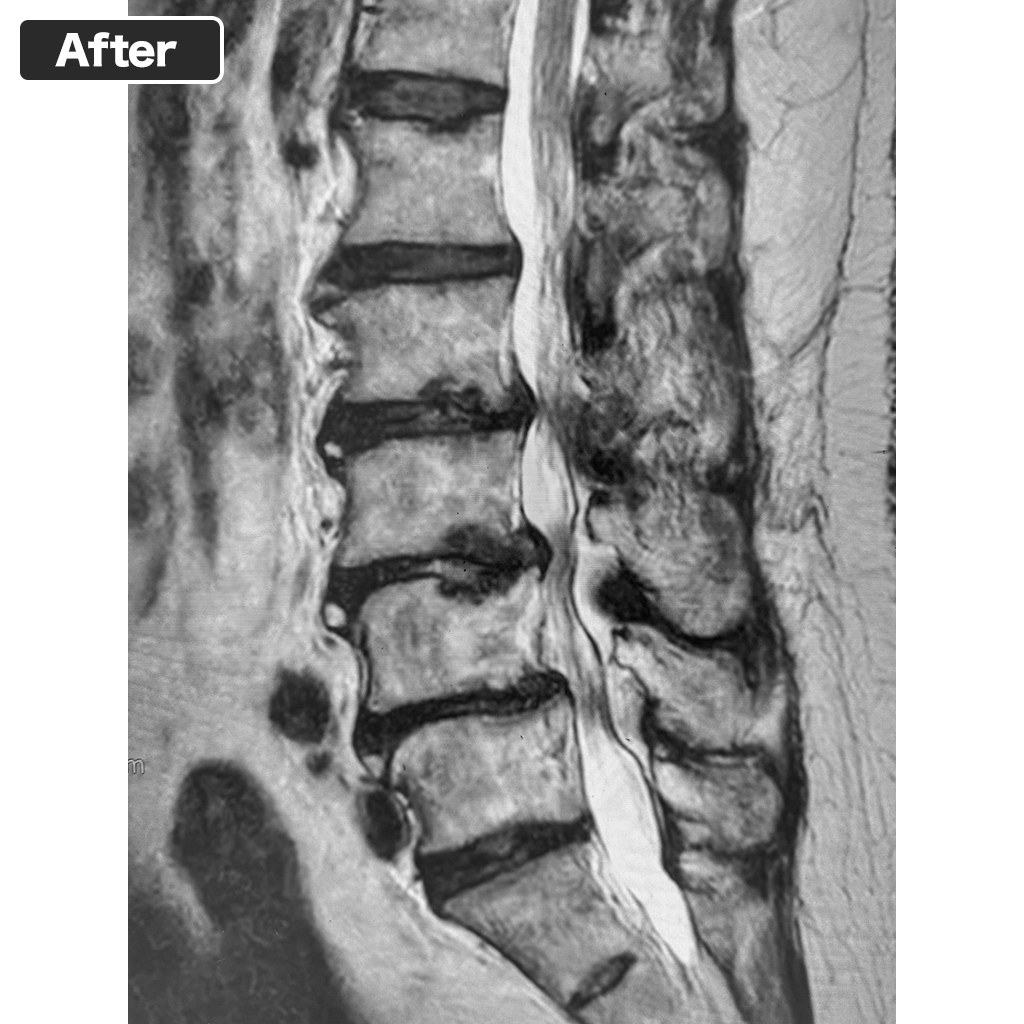

MRI Scan

Today's MRI scan. Improvements such as disc degeneration can be seen. However, subcutaneous fat and visceral fat are significantly more prominent than before treatment.

No neurological disorders of the lower limbs were observed. She reported a dull, tight pain in the right buttock after walking for more than 10 minutes. The MRI scan showed no problems at the Discseel Procedure site, but significant obesity was confirmed. Based on this, it was explained that the currently appearing dull pain is mild, and it is highly likely to improve with weight reduction.